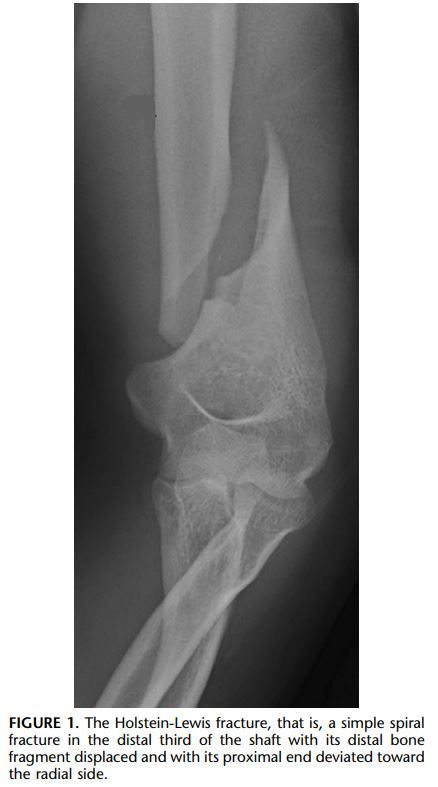

Define Holstein-Lewis fracture? How does it occur

A

The Holstein-Lewis fracture describes a type of humeral fracture

• that is, a simple spiral fracture in the distal third of the shaft

• with the distal bone fragment displaced proximally and the proximal end displaced radially

• with resultant displacement of intermuscular septum

• High association with radial nerve palsy was that the fracture occurs at a point where the radial nerve runs through the lateral intermuscular septum (as opposed to lying in direct contact with the bone) and thus has limited mobility.

• Due to the force of the injury, this potentially lacerating or trapping the radial nerve